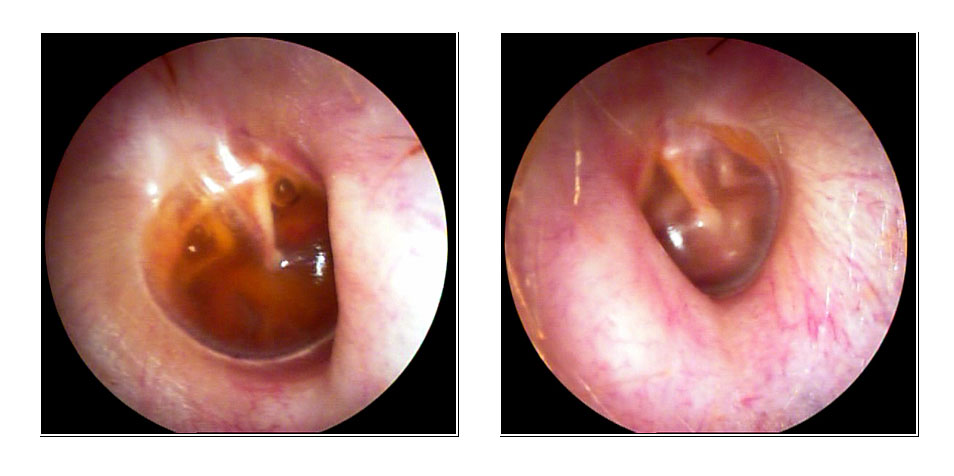

JFC Otitis media serosa.

JFC Otitis media serosa de origen disbárico.

JFC Otitis media serosa izquierda.